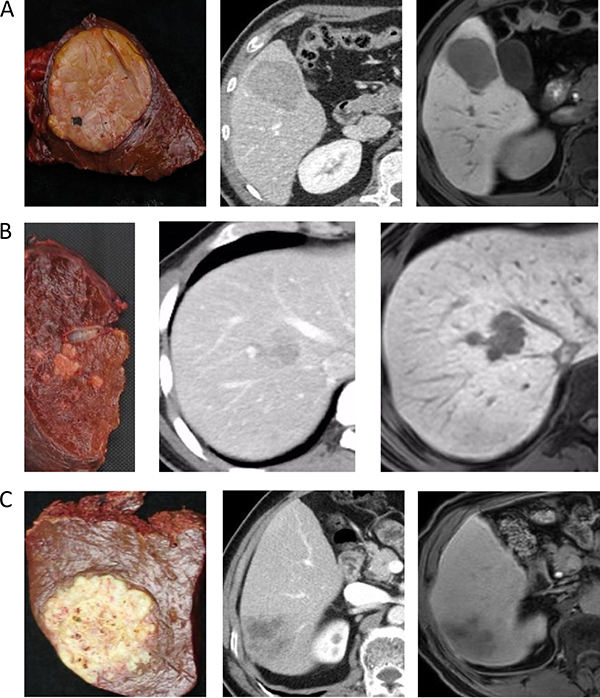

Based on pathological macroscopic examination of the 94 HCCs, six tumors (6.4%) were classified as SN-IM (Figure 1A), 32 (34%) as SN-DM (Figure 1B), 26 (27.7%) as SN-EG (Figure 2A), 21 (22.3%) as CMN (Figure 2B), and nine (9.6%) as IF (Figure 2C). Therefore, 38 nodules (40.4%) were classified as SN and 56 (59.6%) as non-SN. Fifty-one (54.3%) tumors were ≤ 3 cm in size and 43 (45.7%) were > 3 cm. Mean sizes of all tumors, only SN types, and only non-SN types, were 3.7 ± 2.2 cm, 2.9 ± 1.8 cm, and 4.2 ± 2.3 cm, respectively.

Figure 2: (A) A 42-year-old man with cirrhosis related to hepatitis B. The gross classification was SN-EG based on pathological examination. Two images following specimen were arterial phase of CE-CT and hepatobiliary phase of EOB-MRI. (B) A 52-year-old man with cirrhosis related to hepatitis B. The gross classification was CMN based on pathological examination. Two images following specimen were portal phase of CE-CT and hepatobiliary phase of EOB-MRI. (C) A 64-year-old man with cirrhosis related to hepatitis B. The gross classification was IF based on pathological examination. Two images following specimen were portal phase of CE-CT and hepatobiliary phase of EOB-MRI.